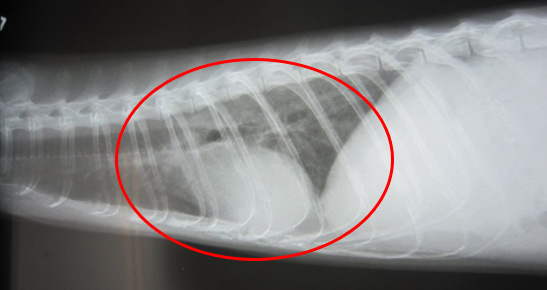

肺水腫(赤丸)を起こした胸部レントゲン写真

脾腫(リンパ腫)の見つかったフェレット

リンパ腫に侵された脾臓(赤丸)